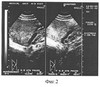

Для подтверждения диагноза проведено исследование согласно предлагаемому способу.

Получены следующие результаты: диаметр маточных вен составил 0,9 см справа и 1,1 см слева; диаметр внутренних подвздошных вен составил 1,7 и 2,0 см соответственно, диаметр яичниковых вен 0,2 и 0,2 см соответственно; диаметр аркуатных вен 0,2 см (фигура 3).

Проведенное исследование позволило обозначить полученные данные как нормальное состояние маточных, яичниковых, внутренних подвздошных и аркуатных вен, что позволило установить правильный диагноз у данного пациента.